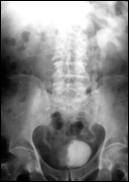

4.1. Radiografia renovezicala simpla si UIV raman examenele de baza pentru diagnosticul etiologic al oricarui pacient cu hematurie. Tumorile vezicale au drept semn radiologic cardinal imaginea lacunara pe cistograma urografica. Tumorile infiltrative pot induce modificari ale supletii peretelui vezical, care devine rigid, inextensibil, retractat etc. in zonele patologice. Ureterohidronefroza sau rinichiul mut sunt rezultatele invaziei si obstructiei ureterelor intramurale induse de tumorile solide, infiltrative (Fig.27,28,29).

Figura 28. Imagine

lacunara de 2,8/2 cm, in aria vezicii urinare, sugerand tumora

vezicala.